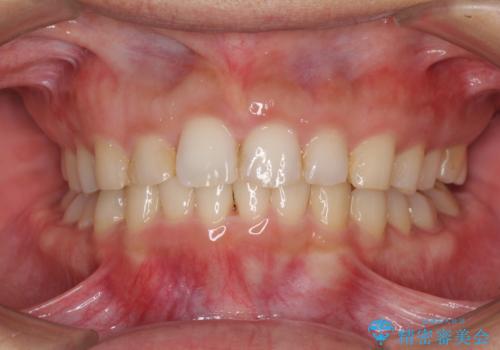

- 深い咬み合わせと前歯のデコボコ、奥歯の欠損を気にして来院された患者様です。

歯列矯正はインビザラインを使用し、矯正治療中の適切な時期に奥歯の欠損部位にインプラントを埋入することとしました。

矯正治療とインプラント治療を同じ歯科医師が担当することで、通常見られるような複数医院を行き来する煩雑さや、複数担当医の見解の違いによる治療の遅滞といった煩わしさは一切なく、スムーズに治療を進めることができました。

安定して咬めるようになり、患者様には大変満足していただきました。